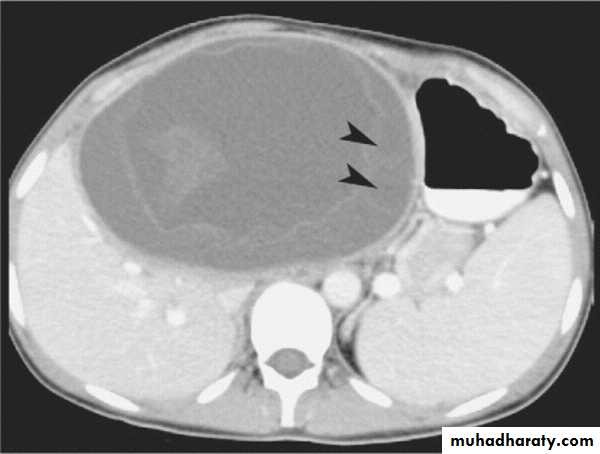

Tissue which concentrate the agent show very high intensity ( they appear white ) on T1 –images .Tissue specific media ,such as iron oxide agents for reticuloendothelial cells imaging .